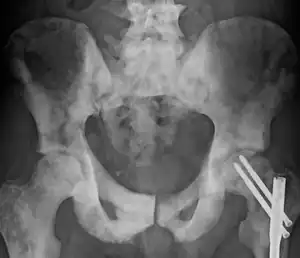

The most important distinction made by any staging system is whether the cancer is confined to the prostate. In the TNM system, clinical T1 and T2 cancers are found only in the prostate, while T3 and T4 cancers have metastasized. Several tests can be used to look for evidence of spread. Medical specialty professional organizations recommend against the use of PET scans, CT scans, or bone scans when a physician stages early prostate cancer with low risk for metastasis.[95] Those tests would be appropriate in cases such as when a CT scan evaluates spread within the pelvis, a bone scan looks for spread to the bones, and endorectal coil magnetic resonance imaging evaluates the prostatic capsule and the seminal vesicles. Bone scans should reveal osteoblastic appearance due to increased bone density in the areas of bone metastasis—the reverse of what is found in many other metastatic cancers.

In men with high-risk localised prostate cancer, staging with PSMA PET/CT may be appropriate to detect nodal or distant metastatic spread. In 2020, a randomised phase 3 trial compared Gallium-68 PSMA PET/CT to standard imaging (CT and bone scan). It reported superior accuracy of Gallium-68 PSMA-11 PET/CT (92% vs 65%), higher significant change in management (28% vs 15%), less equivocal/uncertain imaging findings (7% vs 23%) and lower radiation exposure (10 msV vs 19 mSv). The study concluded that PSMA PET/CT is a suitable replacement for conventional imaging.[96]

-

Sclerosis of the bones of the thoracic spine due to prostate cancer metastases (CT image) -

Sclerosis of the bones of the pelvis due to prostate cancer metastases